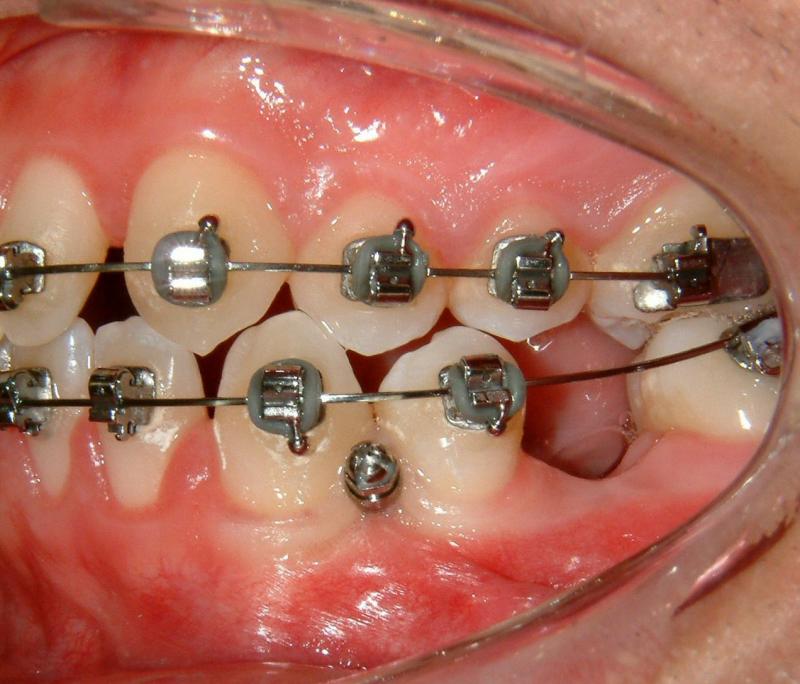

Fig. 7. Loading with NiTi spring (more effective)

© Copyright 2007-2014, Vu Orthodontics. All rights reserved.

The TAD is used as an absolute anchorage to protract LL6 without side effect. (The lower left canine will be moved forward later to achieve Class I canines.) An alternative mechanics may be used with a power arm to achieve a slightly more horizontal force but a bit complicated and less comfort (for the patient).